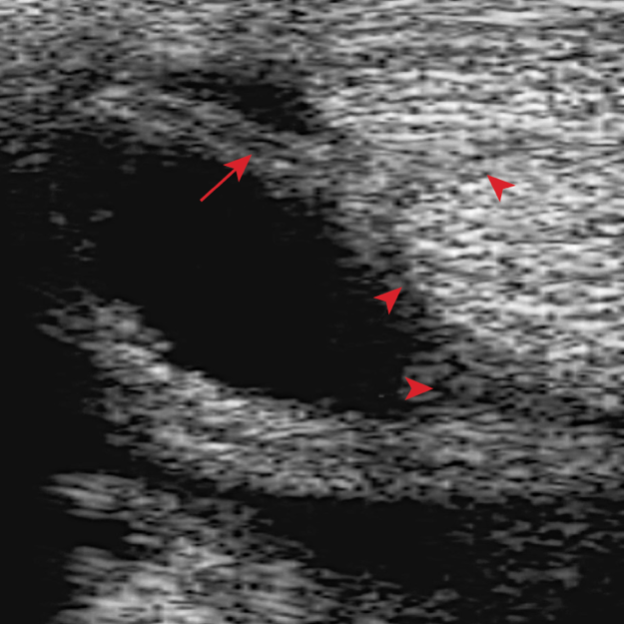

- The sheath is distended by anechoeic fluid. The arrows show the swollen synovial tissue, which is separating the DDFT from the SDFT and its manica flexoria.